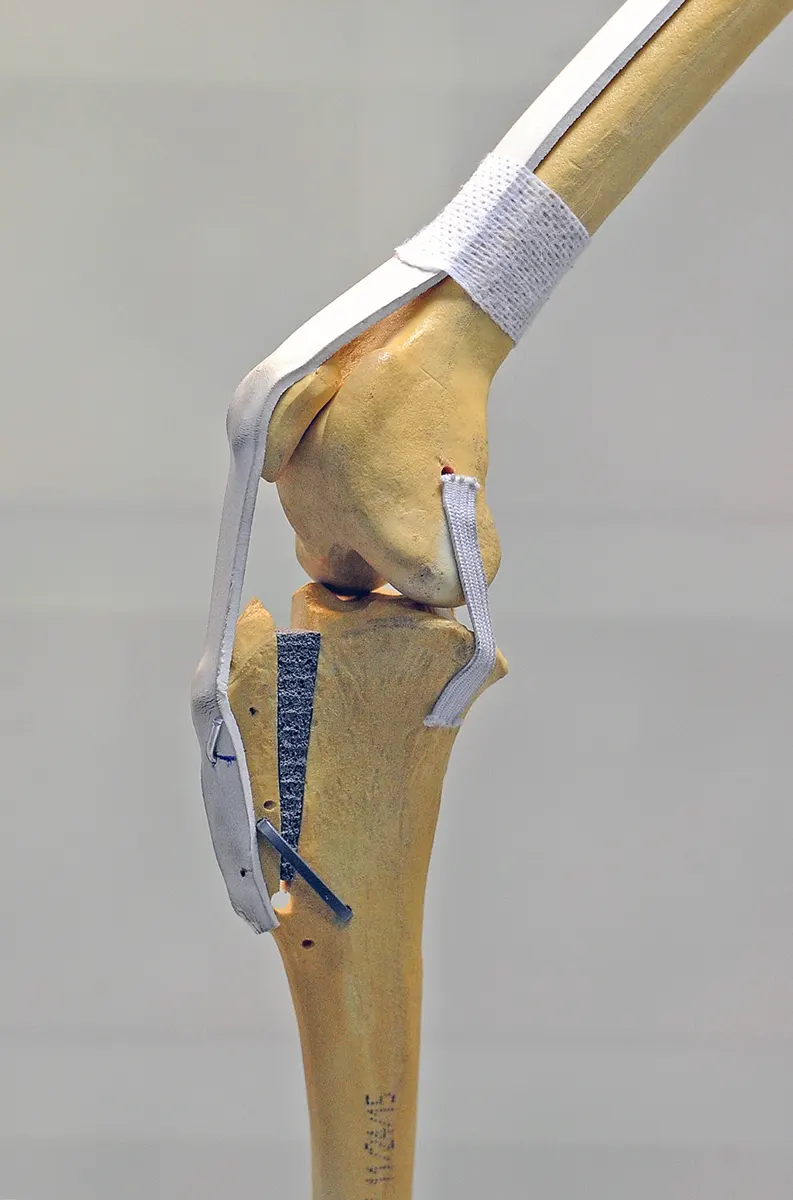

Ove tehnike mijenjaju geometriju koljena na takav način da ligamenti više nisu potrebni za održavanje stabilnosti koljena. Postoji nekoliko tehnika koje uključuju promjenu oblika vrha tibije tako što se napravi rez na kosti i na taj način se postavi u novi položaj:

Ova operacija uključuje pravljenje polukružnog reza na vrhu tibije i rotiranje platoa tibije dok prethodni nagib kosti više ne nestane. Kost se naknadno fiksira odgovarajućom pločicom i vijcima.

Ova operacija uključuje iste principe kao i TPLO, s rezom na tibiji kako bi se omogućila promjena geometrije. Osnovno načelo je da promijenjeni smjer istezanja skupine mišića kvadricepsa proizvodi sile preko zgloba koljena koje neutraliziraju tendenciju bedrene kosti da klizi niz kosinu tibijalnog platoa. I TTA i TPLO imaju za cilj napraviti kut između tibijalnog platoa i patelarne tetive pod pravim kutom, čime se suprotstavlja tendenciji bedrene kosti da klizi niz kosinu tibijalnog platoa. Budući da kost zacjeljuje učinkovitije od ligamenata, ove metode pružaju mnogo veću čvrstoću od metoda popravka ligamenata. Oporavak je puno bolji, psi već 1-3 dana nakon operacije hodaju na bolesnoj nozi. Brz povratak normalnim aktivnostima vrlo je važan za teške pse, atletske pse, pse s blagom hromošću i za pacijente koji imaju bilateralne rupture. Kod takvih se TPLO može izvesti na oba koljena istovremeno. Koja je metoda prikladnija ovisi o individualnim anatomskim karakteristikama životinje. U većini slučajeva obje su metode primjerene.